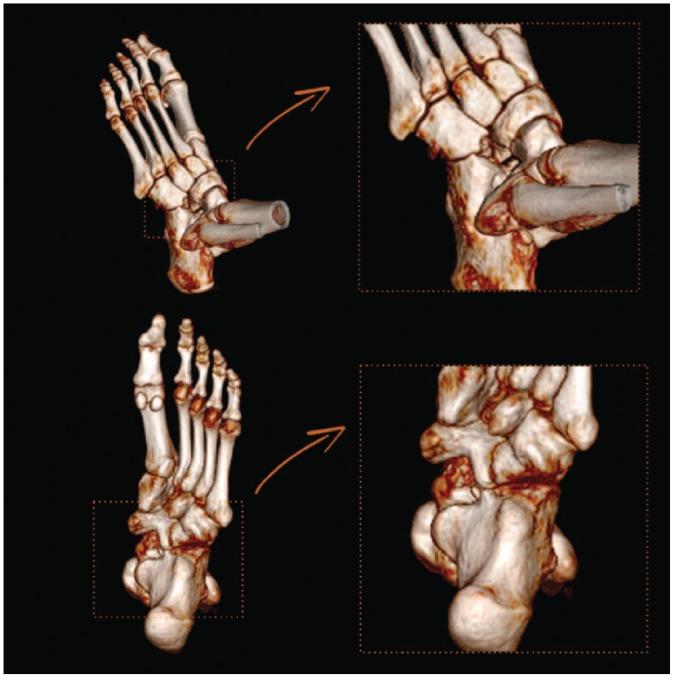

A tarsal coalition is an abnormal connection between two or more tarsal bones caused by failure of mesenchymal segmentation.The two most common tarsal coalitions are calcaneonavicular coalition (CNC) and talocalcaneal coalition (TCC). Both CNC and TCC can be associated with significant foot and ankle pain and impaired quality of life; there may also be concomitant foot and ankle deformity.Initial, non-operative management for symptomatic tarsal coalition commonly fails, leaving surgical intervention as the only recourse.The focus of this article is to critically describe the variety of methods used to surgically manage CNC and TCC. In review of the pertinent literature we highlight the ongoing treatment controversies in this field and discuss new innovations.The evidence-based algorithmic approach used by the authors in the management of tarsal coalitions is illustrated alongside some clinical pearls that should help surgeons treating this common, and at times complex, condition. Cite this article: 2020;5:80-89. DOI: 10.1302/2058-5241.5.180106.

跗骨联合是由于间充质节段化失败导致两块或多块跗骨之间的异常连接。最常见的两种跗骨联合是跟舟联合(CNC)和距跟联合(TCC)。CNC和TCC都可能伴有严重的足踝疼痛和生活质量受损;也可能伴有足踝畸形。对于有症状的跗骨联合,最初的非手术治疗通常无效,手术干预成为唯一的选择。本文的重点是批判性地描述用于手术治疗CNC和TCC的各种方法。在回顾相关文献时,我们强调了该领域持续存在的治疗争议并讨论了新的创新方法。作者在跗骨联合管理中使用的循证算法方法与一些临床要点一起展示,这些要点应有助于外科医生治疗这种常见且有时复杂的病症。引用本文:2020;5:80 - 89。DOI: 10.1302/2058 - 5241.5.180106。